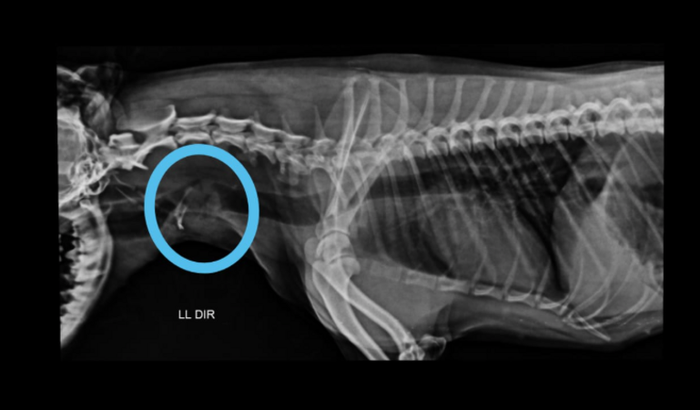

Eu a sou Reusa Almeida, criei essa vaquinha pra tentar salvar a vida da Lolla, nosso bichinho de estimação, a qual foi diagnosticada com tumor na traqueia e necessita arredar o valor para cirurgia e quimioterapia, se não conseguirmos o valor para o tratamento ela vai morrer, precisamos da ajuda de vocês amigos que gostam de animais!